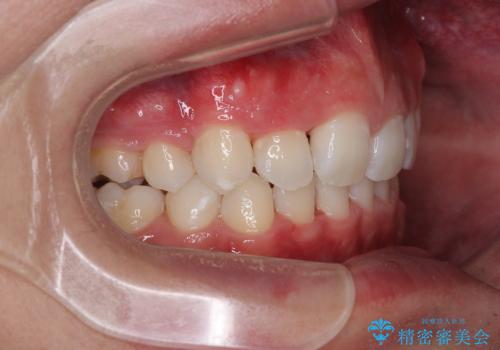

抜歯矯正で叢生と正中のずれを改善|審美装置による矯正症例

- 今回ご紹介するのは、

「全体的なデコボコ(叢生)」「上下の正中のずれ」 を主訴として来院された20代男性の患者様の症例です。

叢生が強く、歯が並ぶスペースが不足していたため、

上下左右の第一小臼歯を抜歯して、矯正治療のための適切なスペースを確保する計画としました。